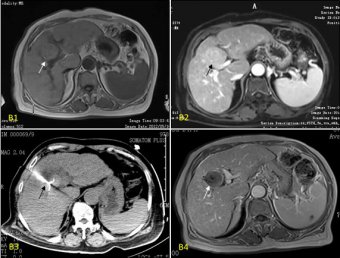

之所以能對肝癌進(jìn)行局部治療,這首先得益于肝臟理想的位置。肝臟位于右上腹部,大頭朝外,右肋部的一大片皮膚與肝臟只是“一墻之隔”。這樣的位置,在運(yùn)用射頻消融微創(chuàng)技術(shù)治療肝癌時(shí)醫(yī)生通過穿刺的方式能夠很容易地進(jìn)到肝臟,在CT或B超的引導(dǎo)下找到癌灶部位實(shí)現(xiàn)靶向性消融。因此,光有理想的位置是不夠的,兩項(xiàng)里程碑式的診療技術(shù)孕育了肝癌局部治療的概念,那就是早期診斷技術(shù)的出現(xiàn)(如肝臟CT、核磁共振)和超聲技術(shù)的應(yīng)用。前者讓人們有能力發(fā)現(xiàn)小肝癌,后者能夠幫助醫(yī)生對肝癌病灶進(jìn)行較準(zhǔn)確的定位,就如同醫(yī)生長了一雙透視眼。

一般認(rèn)為外科切除是肝癌的根治方法,但手術(shù)切除率一直很低。對不能手術(shù)的病人常采用TACE及PEI進(jìn)行治療,但效果常不盡如人意,原因在于其常需要多次治療從而導(dǎo)致肝功能損傷加重,對于少血供的病灶TACE治療效果不佳。射頻消融術(shù)(radio-frequency ablation,RFA)治療肝臟腫瘤于1995年由意大利的Rossi率先應(yīng)用于臨床,是當(dāng)今最新的肝腫瘤導(dǎo)向治療方法之一,許多臨床資料證明:對于治療肝癌,射頻消融術(shù)是一種有效的安全的治療方法。其基本原理是:進(jìn)入組織的電極發(fā)出射頻波,使組織內(nèi)的分子相互撞擊摩擦,產(chǎn)生熱能,使組織細(xì)胞凝固壞死,同時(shí),腫瘤組織對熱的耐受遠(yuǎn)低于正常肝組織,所以腫瘤組織壞死較完全,肝組織得到相應(yīng)保護(hù)。這種手術(shù)可以達(dá)到使患者長期無腫瘤生存,實(shí)現(xiàn)正常工作和生活的目的,并且由于射頻是微創(chuàng)治療,可隨腫瘤反復(fù)發(fā)作進(jìn)行再治療。濰坊市市立醫(yī)院普外科自2000年由國外引入開展運(yùn)用于治療肝臟惡性腫瘤,經(jīng)過10余年的實(shí)踐證實(shí),射頻消融為不能手術(shù)切除的臨床治療困難的肝腫瘤患者提供了很有效的局部治療。》》不清楚該療法是否適用于自己?點(diǎn)擊咨詢在線腫瘤專家

臨床證明對5厘米以下肝癌患者采用射頻消融治療,患者1年生存率為100%,3年生存率達(dá)到了95.1%;對治療5厘米以上射頻消融技術(shù)可消融腫瘤最大直徑為16厘米,這類的患者1年生存率為96.9%。3年生存率達(dá)到了85.1%。射頻消融治療肝癌不僅有生存率高的特點(diǎn),還能實(shí)現(xiàn)預(yù)測控制治療范圍,監(jiān)測熱場的溫度,被譽(yù)21世紀(jì)治療肝癌最具應(yīng)用前景的治療手段。

成功治療案例: